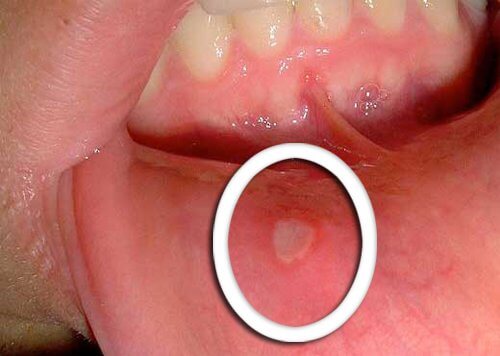

- Det tidligste symptom på svælg kræft er små sår, der ikke heler.

- Det er typisk, at rødt eller hvidt vises på tungen, tandkødet eller på læberne.

- Vær opmærksom på eventuelle usædvanlige ændringer, der ikke forbedres på et par dage og gør opmærksom på dem overfor din læge.